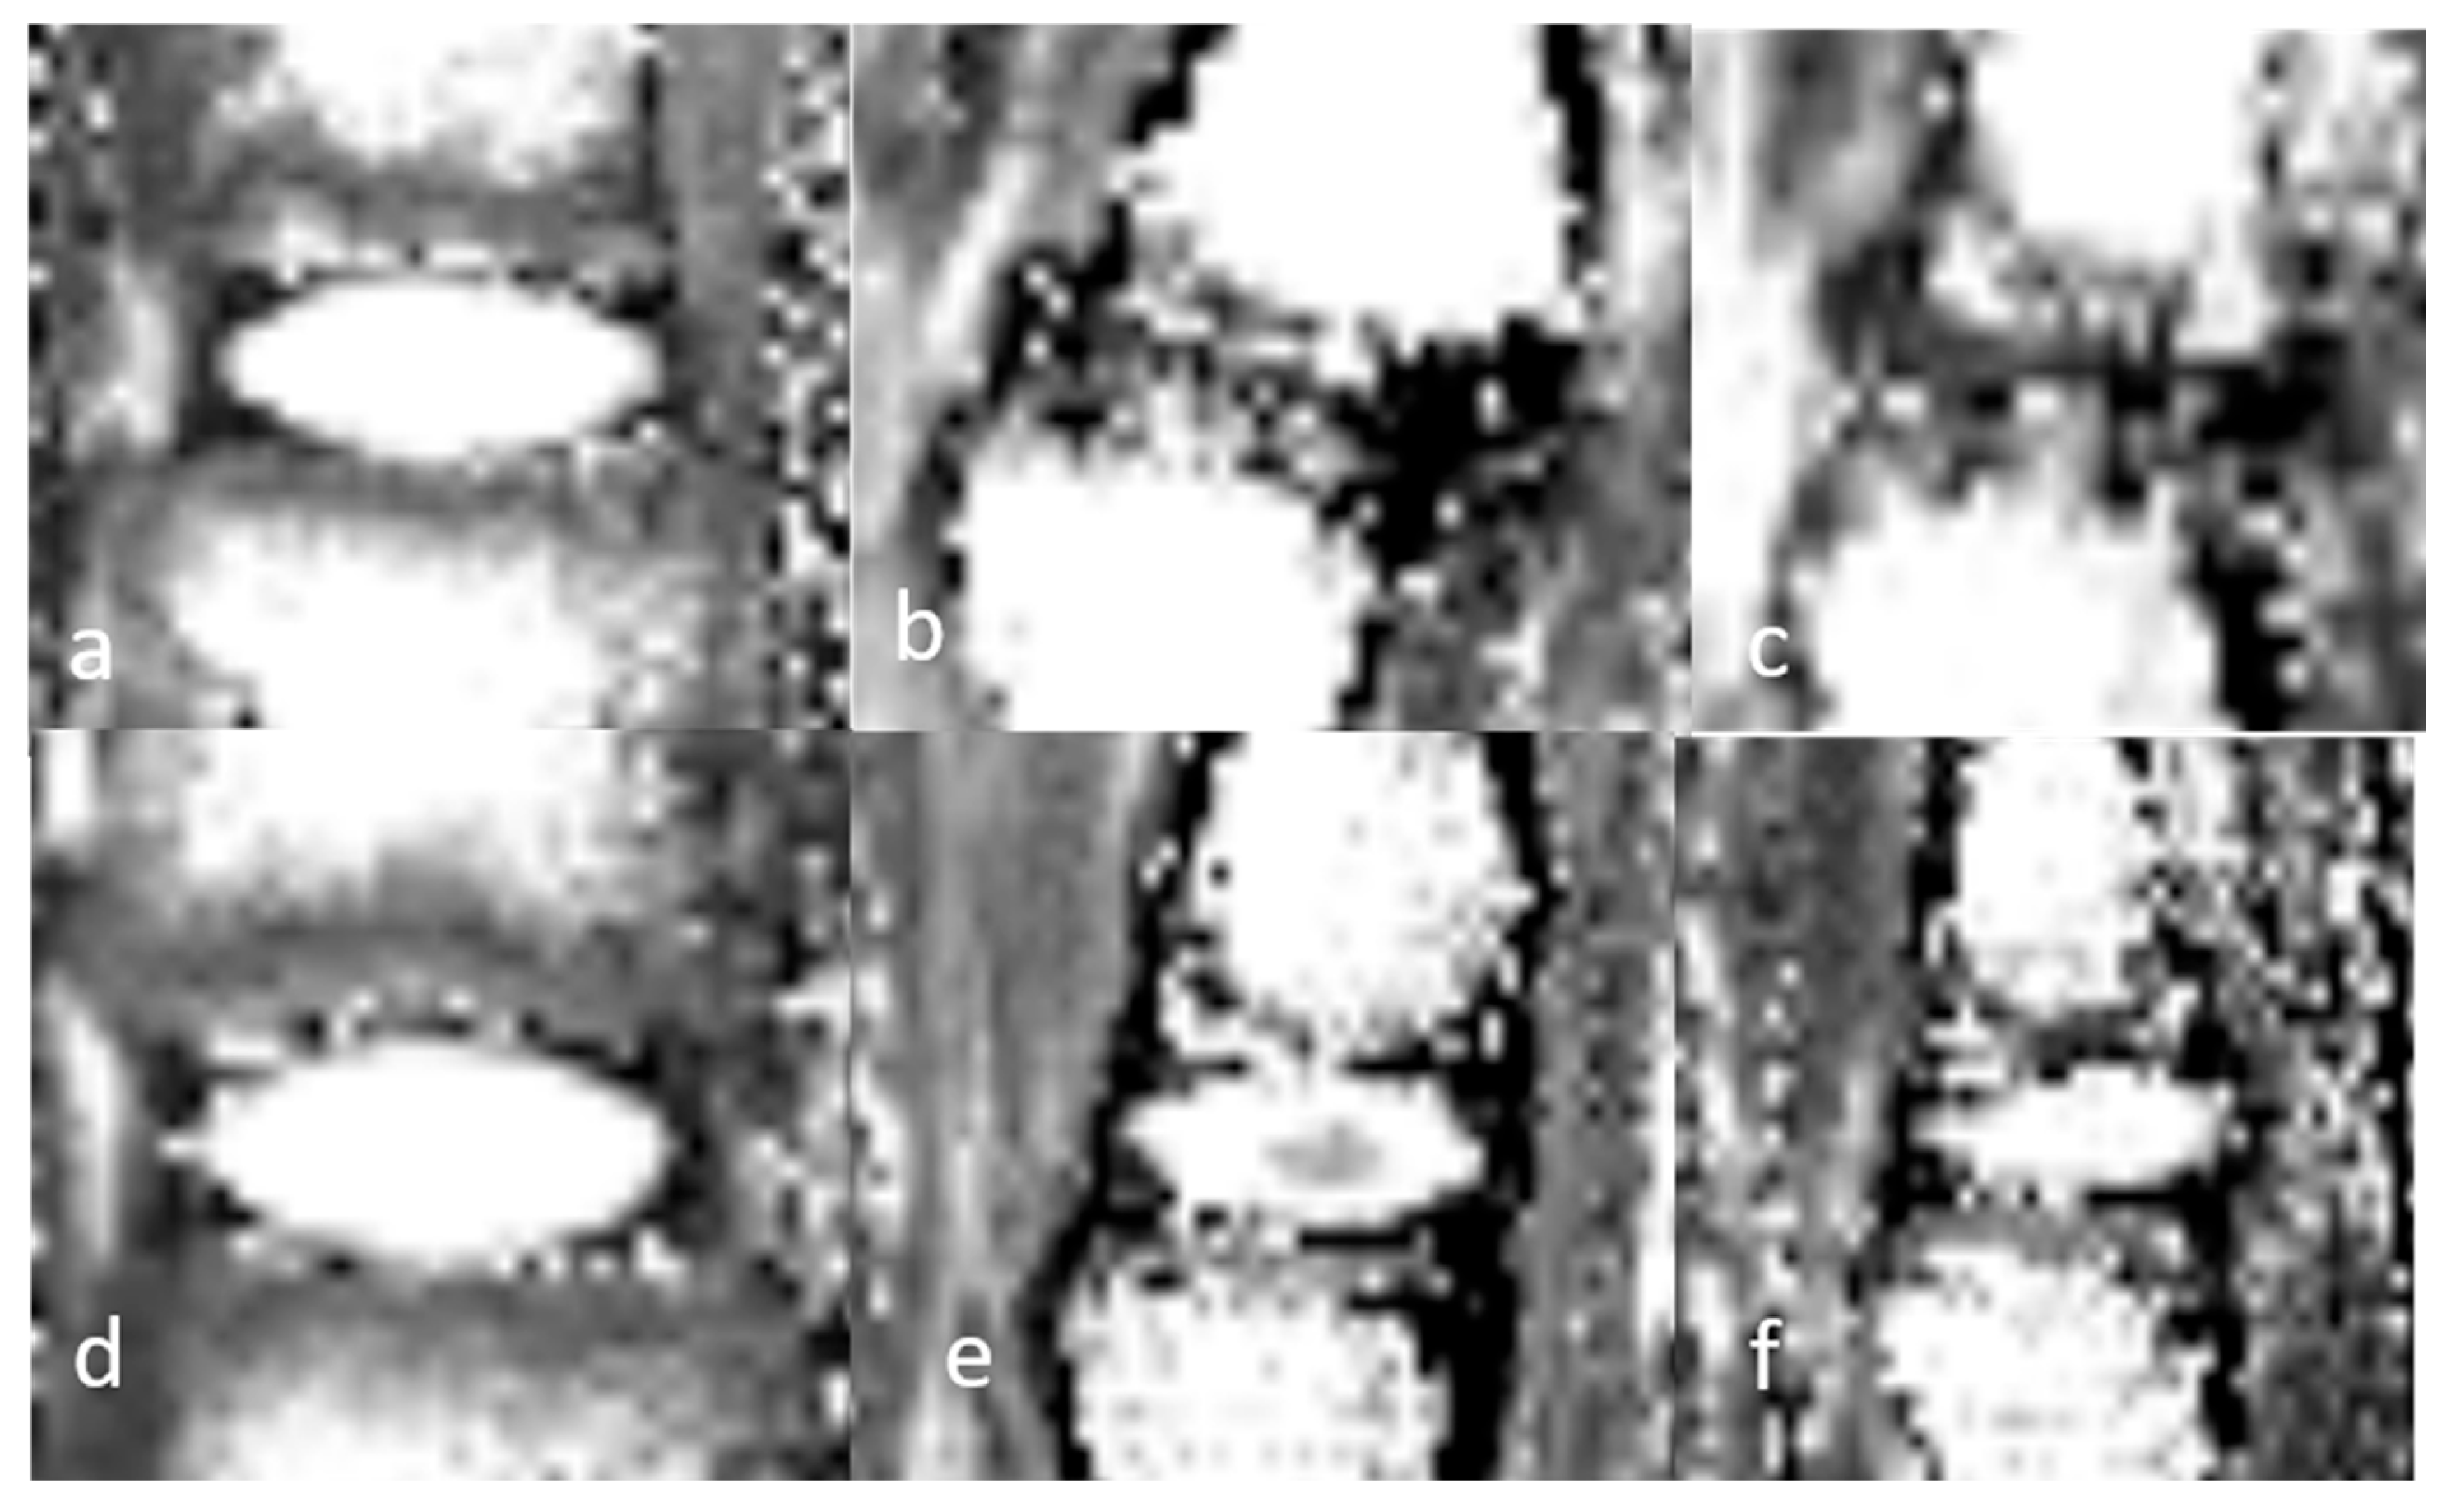

3.1.3. Quantitative Analysis of the Normal DVC (Table 4)

3.1.4. Quantitative Analysis of the DVC in DDD Rats (Table 4)